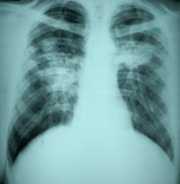

Small Parenchymal Opacities in Coal Workers' Pneumoconiosis